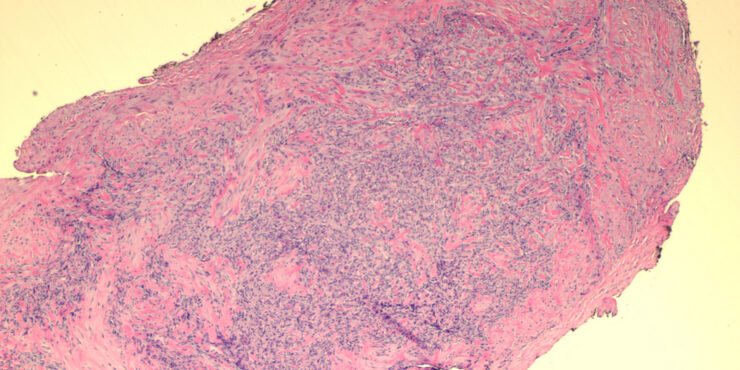

Read MoreMycobacterial panniculitis = التهاب السبلةالشحمية بالمتفطرات Infections with Nontuberculosis Mycobacteria Among the nontuberculosis, nonleprosy mycobacterial infections of the skin, those caused by M. marinum are the most common among nonimmunosuppressed people . Unlike M. tuberculosis, which is transmitted from person to person, nontuberculosis mycobacteria are abundant in nature, in soil and water, and contact is […]